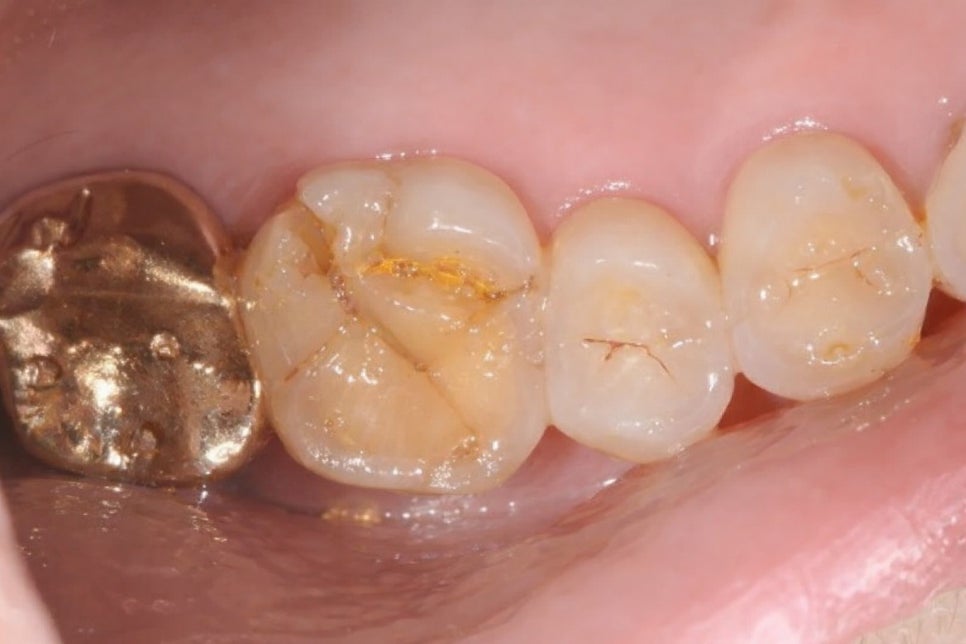

🔻 또한 신경치료를 받은 곳을

크라운으로 보호하지 않은 채 오래 방치한 경우

crack이 발생할 위험이 높아집니다.

따라서 당산 보존치과 는 끝까지 치료받는 것이

무엇보다 중요하다 말씀드리곤 합니다.